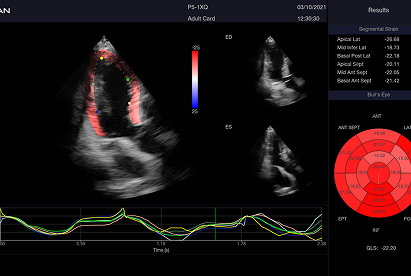

Incluye además eLV para análisis cardíaco avanzado, eOB para mediciones obstétricas automáticas y eLearn como guía interactiva.